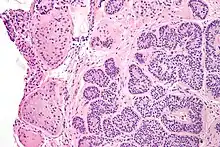

| Micrograph of a Sertoli cell nodule. H&E stain. | |

Sertoli cell nodules are unencapsulated nodules that consist of:[2][3][4]

- cells arranged in well-formed tubules (that vaguely resemble immature Sertoli cells), with

- bland hyperchromatic oval/round nuclei that are stratified, and

- may contain eosinophilic (hyaline) blob in lumen (centre).

Micrograph of a Sertoli cell nodule. H&E stain.